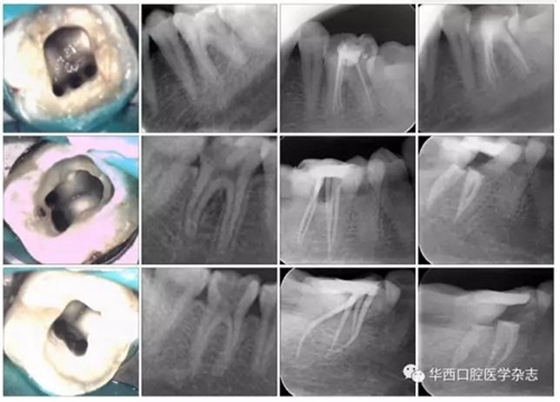

下頜第一恒磨牙MMC的三種可能解剖形態(tài)見圖4。

從上至下依次為“獨(dú)立”、“歧狀”和“融合”解剖型。

第一列:MMC 顯微鏡 ×16;

第二列:術(shù)前片;

第三列:試尖片;第四列:根充片。

圖4下頜第一恒磨牙MMC的三種可能解剖形態(tài)(Pomeranz分類)

在確定的17顆牙的近中三根管中,顯示“獨(dú)立”解剖(獨(dú)立根尖孔)的2顆(11.8%);顯示“歧狀”解剖(沒(méi)有單獨(dú)的根管口)6顆(35.3%);顯示“融合”解剖(具有單獨(dú)的根管口,最終在根尖方向融入到其中一個(gè)主根管)9顆(52.9%)(圖4)。在顯示“融合”解剖的9顆牙的近中三根管中,6顆融合到近中舌側(cè)根管,3顆融合到近中頰側(cè)根管。